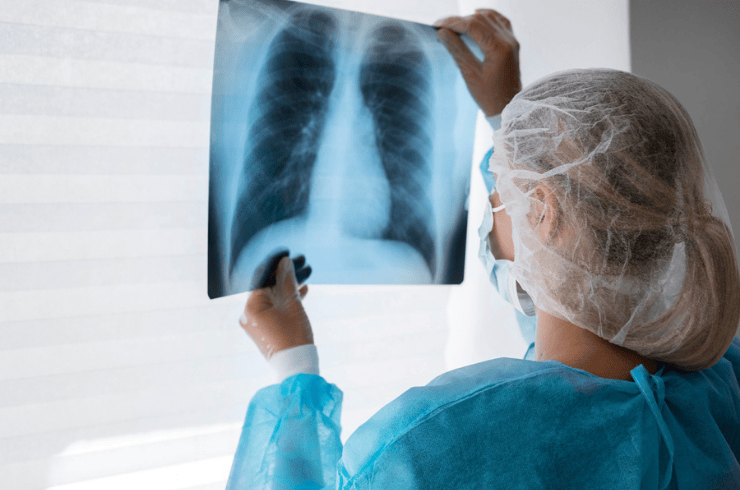

Digital X-Ray services at Ajey Diagnostics Pvt. Ltd. are designed to deliver fast, clear, and accurate imaging for diagnostic and occupational health needs. With advanced DR (Digital Radiography), CR (Computed Radiography), and 100 mA X-ray systems, we provide high-quality chest and skeletal imaging that supports early detection of respiratory issues, injuries, and workplace-related health conditions. Our technology ensures minimal radiation exposure while maintaining excellent image clarity.

Our X-ray services play a crucial role in corporate and statutory medical examinations, especially for industries where workers may be exposed to dust, fumes, chemicals, or physical strain. Digital imaging enables quick assessment of lungs, bones, and joints, helping detect conditions such as tuberculosis, silicosis, fractures, arthritis, and other occupational health risks. Every scan is interpreted by qualified radiology experts to ensure dependable results.

At Ajey Diagnostics, we prioritize patient comfort and efficiency with a well-equipped X-ray room, trained technicians, and strict quality protocols. Our workflow ensures minimal waiting time and smooth coordination with other diagnostic tests. Whether for routine health screening, statutory examinations, or clinical evaluation, our Digital X-Ray services provide reliable imaging support to keep your workforce healthy and compliant.